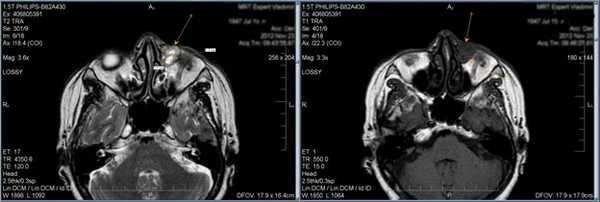

8. Каротидная кавернозная фистула.

На аксиальной Т1-взвешенной МР-томограмме визуализируется расширение правой и левой верхних глазничных вен (стрелки).

9. Тромбоз верхней глазничной вены.

Корональная Т1-взвешенная МР-томограмма демонстрирует гиперинтенсивный сигнал в проекции расширенной левой верхней глазничной вены (стрелка), свидетельствующий о тромбозе. Маленькая стрелка указывает на смещенный влево зрительный нерв.